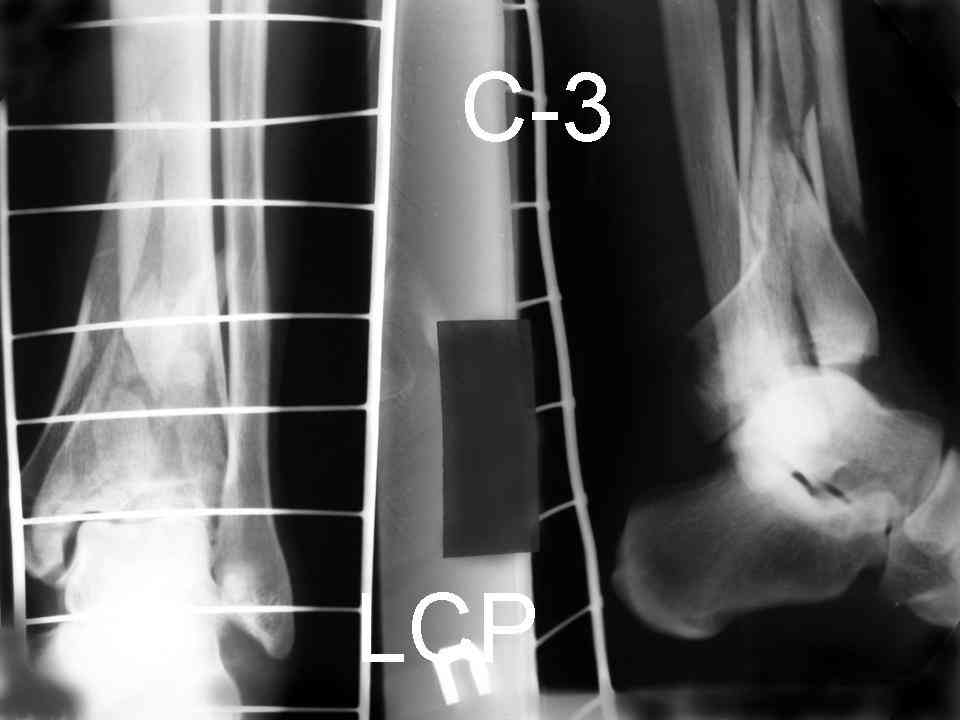

Re: Perelom N/3 kostei goleny

Послала ещё два снимка, если не пройдут, пошлю ещё. Дрягин. Если есть вопросы, готов ответить.